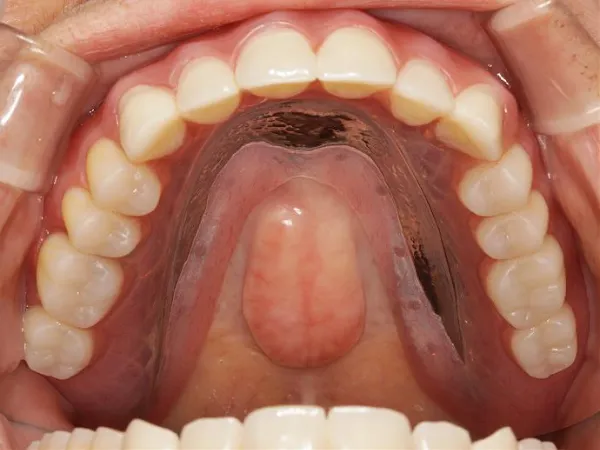

歯やアゴの粘膜の型をとって、すべての歯の向きや状態、アゴの形などがわかりやすくなるような型枠を作成します。